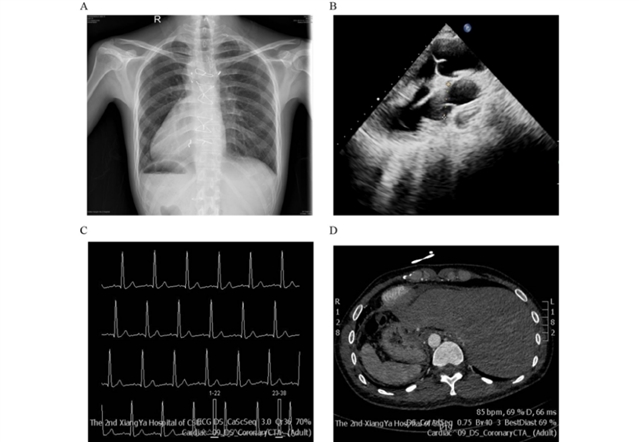

研究纳入一名30岁男性先证者,其临床表现为复杂先天性心脏病(包括右室双出口、室间隔缺损、卵圆孔未闭、肺动脉狭窄)、镜面右位心及内脏异位症(图1)。进一步检查发现,患者存在弱畸精子症,精子长度较对照组平均缩短10μm,且精子活力、前向运动能力及正常形态率均低于参考值。家系分析显示,先证者父母为近亲结婚(表型正常),均携带MYO1D基因杂合变异,而先证者为纯合变异(NM_015194.2: exon12:c.1531G>A:p.D511N),Sanger测序验证了该结果(图2)。氨基酸序列分析显示,511位天冬氨酸在多物种中高度保守,提示其功能重要性。

图1 患者的临床表现